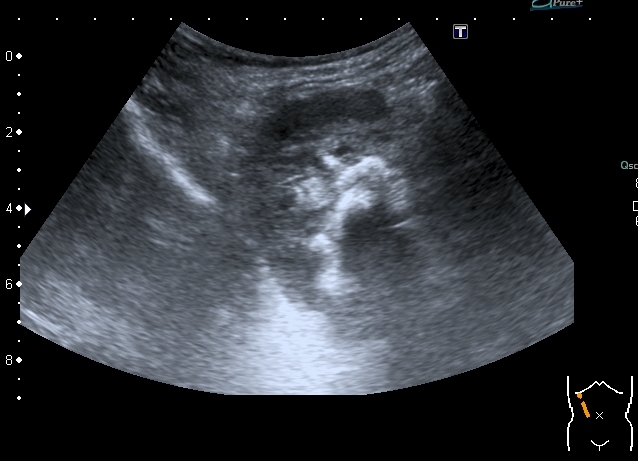

Сокращённый мочевой пузырь

Он же в поперечном скане